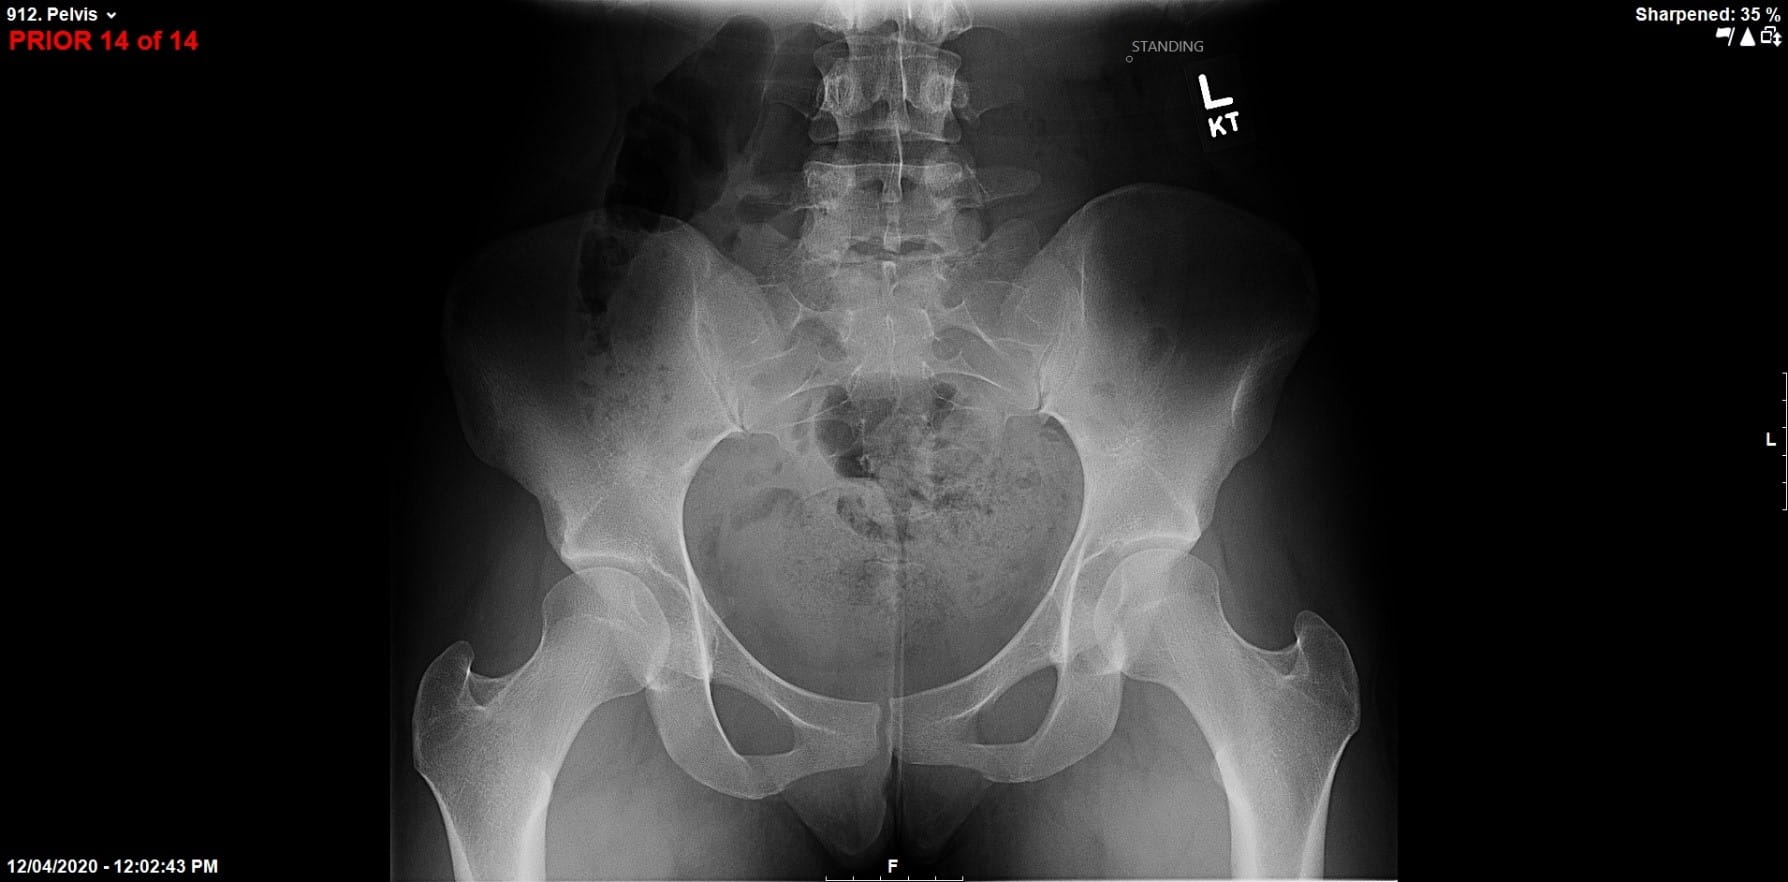

For the past decade, two renowned surgeons at University Hospitals have partnered to advance their novel combined surgical approach to treat concomitant femoral acetabular impingement (FAI) and hip dysplasia.

Dr. Salata performs the first stage of the surgery, using arthroscopic techniques to round the femoral head, improve offset and repair labral damage resulting from FAI. The Director of the Joint Preservation and Cartilage Restoration Center and Division Chief of Sports Medicine at University Hospitals Cleveland Medical Center, he is also a Professor at the School of Medicine and Associate Orthopedic Team Physician for the Cleveland Browns.

Without disrupting the sterile surgical field, Dr. Wetzel next scrubs in and employs an open technique to deepen and reorient the hip socket. “Where University Hospitals differs from other places around the country is that we have been able to maintain a partnership that requires two very vastly different skill sets to execute this surgery to the highest level of efficiency and skill,” he says. “We have the ability to rely on each other as knowledge sources and eliminate single-surgeon bias when we discuss treatment plans with patients.”